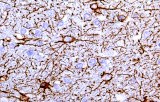

CE/IVD antibodies for immunohistochemistry (IHC) in neuropathology are validated in vitro diagnostic reagents used to detect specific neuronal and glial antigens in formalin-fixed paraffin-embedded (FFPE) tissue. Peer-reviewed neuropathology literature supports their role in improving reproducibility and diagnostic accuracy in central nervous system (CNS) diseases, including brain tumors and neurodegenerative disorders.

Targeted proteins such as GFAP, OLIG2, NeuN, synaptophysin, neurofilament, and Iba1 reflect astrocytic, oligodendroglial, neuronal, and microglial lineages. Their expression patterns are widely used in peer-reviewed studies to define CNS cell identity, differentiation state, and neuroinflammatory or degenerative processes.

CE/IVD IHC antibodies support CNS tumor classification (gliomas, embryonal tumors, metastases), assist in differential diagnosis, and help identify proteinopathies associated with Alzheimer’s disease and other neurodegenerative conditions. They are routinely used in biomarker panels for tumor grading and diagnostic stratification in neuro-oncology.